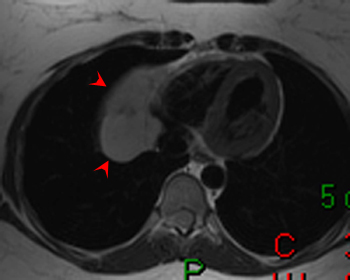

Answer: D. Stanford Type A Aortic Dissection. This image shows a dilation of the ascending aorta with a normal caliber descending aorta. An intimal flap can clearly be seen in the ascending aorta (arrow) representing an aortic dissection. There is no wall thicken to suggest an intramural hematoma. This aortic dissection is Stanford Type A since it includes the ascending aorta; Type B would include only the descending aorta. Somner T, Freshke W, Holzknecht N et al. Aortic dissection: a comparitive study of diagnosis with spiral CT, multiplanar transesophageal echocardiography, and MR imaging. Radiology 1996; 199(2): 347-52.17) What abnormality is seen on the T1-weighted (left) and T2-weighted (right) images below? ![]() Answer: A. Pericardial Cyst. These images show a homogenous mass (arrowheads) in the right cardiophrenic angle that is adherent to the pericardium and has relatively high signal on T2-weighted images and relatively low signal on T1-weighted images. The signal characteristics and cardiophrenic location are classic for a pericardial cyst. A lipoma would have signal characteristics that mirror subcuanteous fat. A myxoma would be within the heart itself. A pericardial mesothelioma would be more heterogenous. Constrictive pericarditis normally appears as a thickening of the pericardium, but these images clearly show a mass. Breen, JF. Imaging of the Pericardium. Journal of Thoracic Imaging 2001; 16(1): 47-54.18) This image is most consistent with what diagnosis? ![]() Answer: C. Amyloidosis. This image shows DHE sparing the subendocardium in a somewhat patchy distribution (arrows); this is most consistent with amyloidosis. There is no pericardial thickening to suggest constrictive pericarditis. Transmural and subendocardial infarctions would have DHE in a coronary artery distribution. VSD would demonstrate a connection between the ventricles. Maceira AM, Fisher NG, McKenna WJ, Pennell DK, et al. Cardiovascular magnetic resonance in cardiac amyloidosis. Circulation 2005; 111(2): 186-93.19) What abnormality is seen in the sagital view below? ![]() Answer: C. Aneurysm of the aortic root. This image shows a fusiform aneurysm of the aortic root (arrows) in a patient with Marfan�s syndrome. Additionally, there is loss of the distinctness of the sinotubular junction (arrowheads), a common finding in patients with Marfan's syndrome. Compare with the normal aorta in the image to the right (coronal image). These patients need periodic examinations to determine the necessity of prophylactic surgery to prevent aortic dissection. There is no intimal flap seen, so the patient has not yet suffered a dissection. Fattori R, Bacchi Reggiani L, Pepe G, Napoli G, Bna C, Celletti F, Lovato L, Gavelli G. Magnetic resonance imaging evaluation of aortic elastic properties as early expression of Marfan syndrome. Journal of Cardiovascular Magnetic Resonance 2000; 2(4): 251-6.20) What abnormality is seen in the DHE image below? ![]() Answer: C. Microvascular obstruction. There is a focus of unenhanced subendocardium (arrow) surrounded by transmural DHE in the anteroseptum. This unenhanced subendocardium represents an area of microvascular obstruction (MO) within a transmural infarction. Gadolinium contrast media cannot enter an area of MO because the vessels are destroyed. Wu KC, Kim RJ, Bluemke DA, et al. Quantification and time course of microvascular obstruction by contrast-enhanced echocardiography and magnetic resonance imaging following acute myocardial infarction and reperfusion. Journal of American College of Cardiology 1998; 32:1756-1764. |